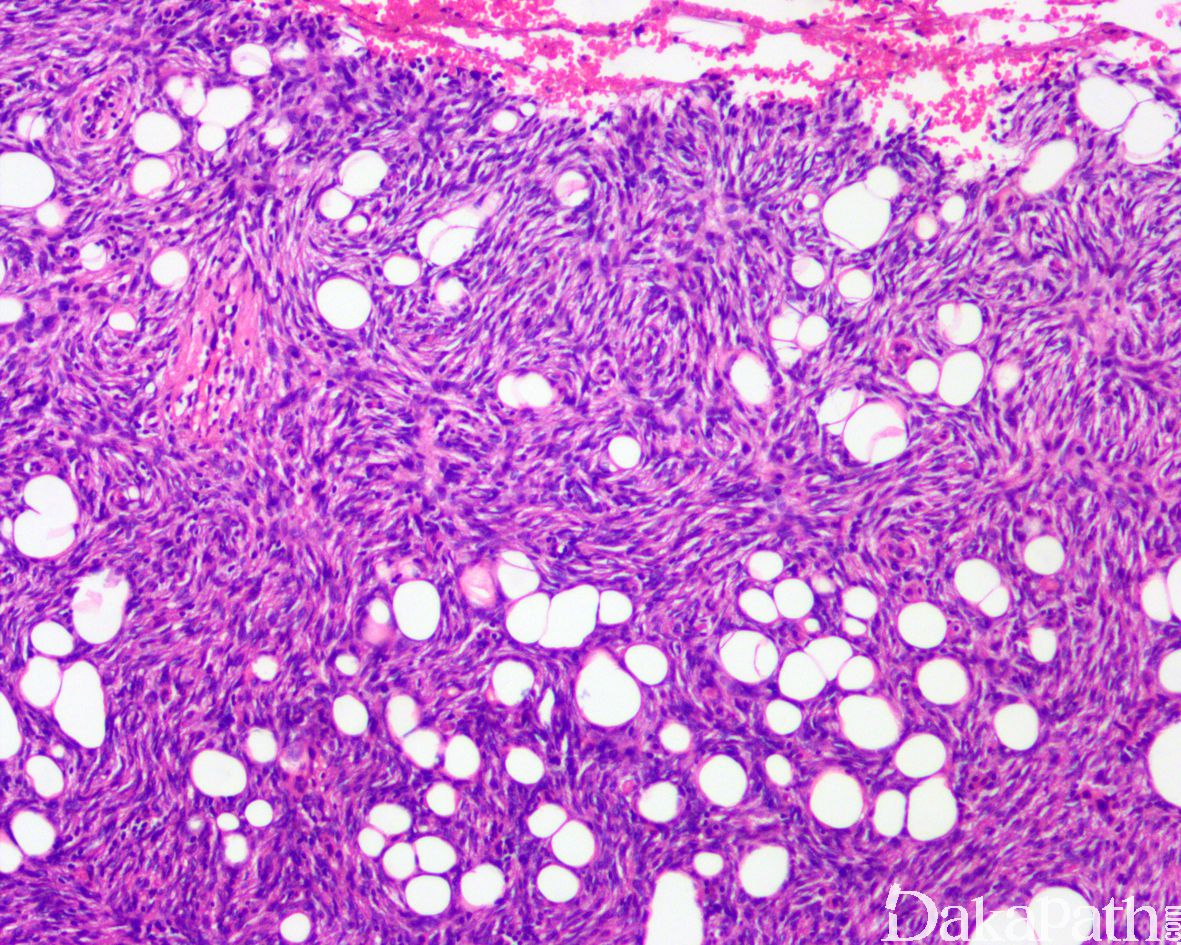

肿瘤主要位于真皮层,弥漫浸润性生长,浸润脂肪组织形成特征性的蜂窝状或蕾丝样 (或称花边样)浸润图像;

部分病例可见局灶的间质黏液变性,黏液区瘤细胞缺乏席纹状结构,瘤细胞呈星芒状,间质微血管网增生明显;

成脂肪的孤立性纤维性肿瘤:皮下发生为主,病变多界限清楚,脂肪组织为肿瘤的一部分而非浸润而累及的脂肪, 以血管外皮瘤样结构为主,仅见局灶的席纹状结构,免疫组化染色除了表达 CD34 之外,尚特征性的表达 STAT6 可资鉴别。